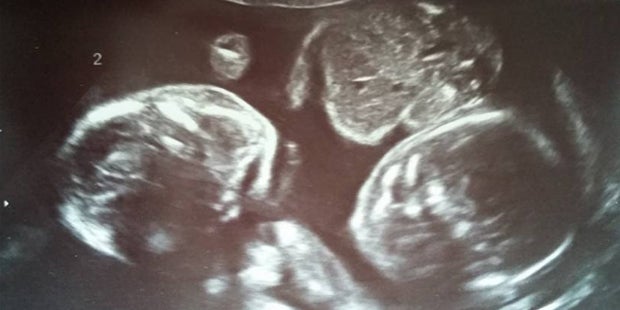

Wenig später machten die Ärzte beim Ultraschall eine unschöne Entdeckung. In diesem Fall handelte es sich um eine monochorial-monoamniale Schwangerschaft. Dies bedeutet, dass die Zwillinge sich Fruchtblase und auch Plazenta teilten. Durch die fehlenden Eihäute zwischen den Kindern kann es bei einer solchen Schwangerschaft leicht zu Nabelschnurumwicklungen kommen. Folglich sind nicht nur Komplikationen bei der Geburt möglich, sondern es können auch Wachstumsretardierungen auftreten. Diese häufigen Fehlentwicklungen können den Tod des Kindes im Mutterleib herbeiführen. Die Überlebenschancen der Zwillinge Blake und Rowan waren aus diesem Grund gering.

Um Komplikationen zu verhindern, musste Hayley regelmäßig eine Kontrolle beim Ultraschall machen. Dort zeige sich Erstaunliches. Die Zwillinge bewegten sich kaum. Auf den Ultraschallbildern sah es so aus, als ob sich die beiden aneinander festhalten oder kuscheln würden. So schafften es die kleinen Kämpfer im achten Monat unbeschadet per Kaiserschnitt zur Welt zu kommen.